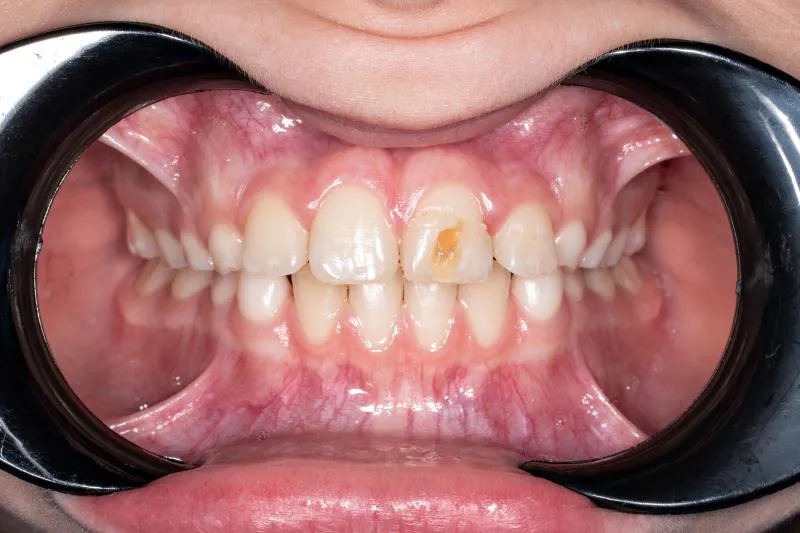

Forskere fra Københavns Universitet og Rigshospitalet har sammen med brasilianske kolleger publiceret en retrospektiv kohorteundersøgelse om forekomsten af skader på permanente incisiver efter eksartikulation af primære incisiver. Ved gennemgang af journaler fra 2.922 børn, der i perioden 1998-2019 var blevet behandlet for tandtraumer på en universitetsklinik i São Paulo, fandt man 194 børn med i alt 266 eksartikulerede incisiver, og i 115 tilfælde (43,2 %) kunne der konstateres skader på de efterfølgende permanente tænder. Der blev registreret 15 forskellige typer af tanddannelsesforstyrrelser, og de hyppigst forekommende var hvidlige emaljeopaciteter og afgrænsede opaciteter med emaljehypoplasi.

Risikoen for permanente skader var højest, hvis børnene var 0-2 år på traumetidspunktet (56,9 %), og mindst, hvis de var over fire år (21,3 %). Risikoen for skader var højere efter eksartikulation i underkæben end i overkæben (RR = 1,45), og hvis flere end to tænder blev eksartikuleret (RR = 1,57).